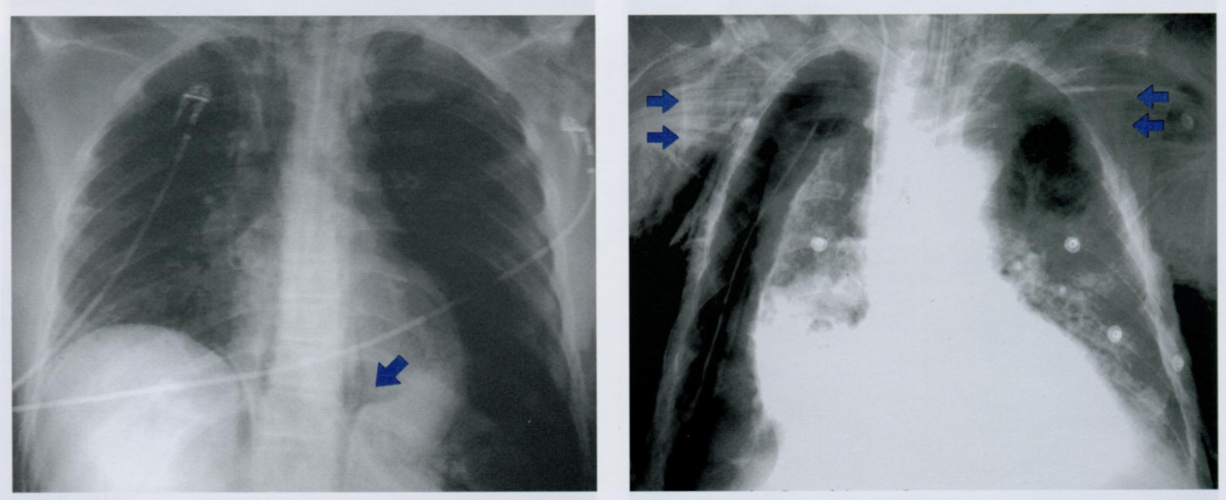

Данный снимок выполнен у одного и того же пожилого пациента с интервалом в 3 месяца. Обратите внимание на неравномерное утолщения ребер, отмеченные стрелками.

Дайте характеристику находке. Какие структуры грудной клетки наиболее часто поражаются?

Как отличить данную находку от костной мозоли после перелома?

Гематогенные метастазы - наиболее часто встречающиееся опухоли скелета грудной клетки у пожилых людей.

Особенно подозрительны кости, которые содержат костный мозг - ребра, грудина и позвоночник.

На повторном снимке мы видим прогрессию кортикального дефекта и увеличение размера метастаза.

На снимке слева ниже для сравнения показано веретенообразное утолщение после перелома ребра (костная мозоль), которое не сопровождается остеолическими изменениями кости. Важно визуально отличать костные мозоли и метастазы на ребрах.

На правом снимке также представлены участки остеолиза на телах грудных позвонков +/- снижение их высоты (отмечено стрелкой). При этом эти изменения не видны в ЗПП, поэтому показана БП.